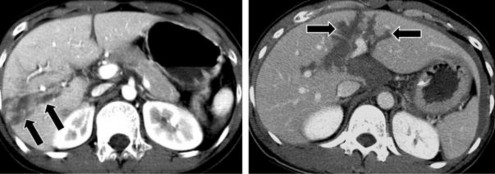

Hình 1.7: Tụ máu dưới bao gan có dạng hình liềm (mũi tên dài) hay thấu kính và các khối máu tụ trong nhu mô gan (mũi tên ngắn).

Nguồn: Shanmuganathan K, Mirvis SE [21].